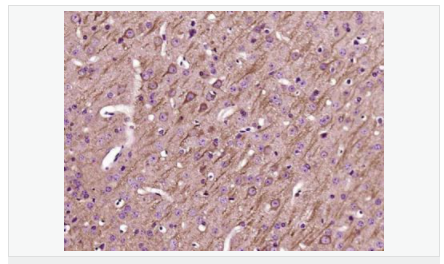

| 產(chǎn)品應(yīng)用 | WB=1:500-2000 IHC-P=1:100-500 IHC-F=1:100-500 IF=1:100-500 (石蠟切片需做抗原修復(fù)) not yet tested in other applications. optimal dilutions/concentrations should be determined by the end user. |